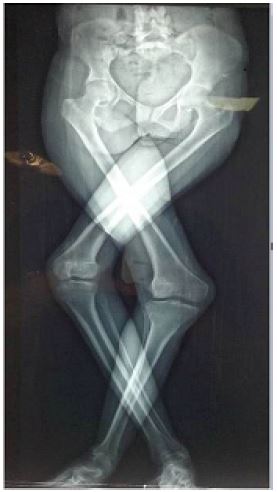

A 27-year-old woman presented to our department with severe bilateral genu valgum (Figure 1). The patient had been suffering from kidney failure since the age of nine and able to walk with a scissor gait. The knee’s range of motion was quite normal with a mild lack of extension (extension/ flexion: 10/120°of the right and left knee). Physical examination noted a slack medial collateral ligaments, dislocated patellae with no evidence of torsional tibial or femur abnormalities.

Lower limb x-ray showed the importance of femoro-tibial angle (FTA: Right limb 48°/ Left 56°), bilateral lateral femoral condyle and tibial plateau hypoplasia (Figure 2). This case was classified as a sever deformity according to the Keblish classification.

Figure 1: Clinical aspect with unusual crossing leg stabilizing severe deformity.

Figure 2: Long-leg standing weight-bearing x-ray.